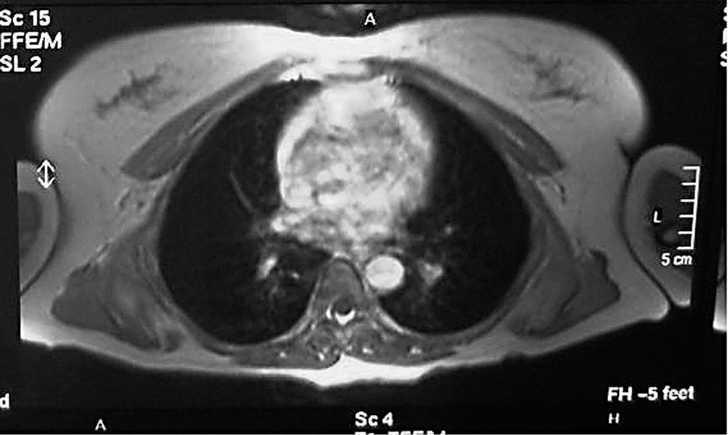

Mujer de 40 años, fumadora, que consultó por un bulto no doloroso en región escapular de un año de evolución que aumentaba de tamaño, alcanzando 7 cm de diámetro. La RMN mostró una tumoración en músculo serrato mayor derecho, en contacto con la pared costal debajo del músculo dorsal ancho que se continúa hasta el músculo subescapular (fig. 1). Era compatible con tumor de alta agresividad, descartandose fibrohistiocitoma u otro sarcoma de partes blandas. Se realizó una biopsia incisional, en anatomía patológica con el resultado de ED. Se practicó una resección marginal, encontrando el tumor ampliamente adherido a la pared torácica y escápula. Se confirmó el diagnóstico de ED tras el análisis de la pieza.

Figura 1. Corte coronal de resonancia magnética nuclear (RMN) en el que se observa un elastofibroma dorsi; se aprecia la tumoración en contacto con la pared torácica bajo el músculo dorsal ancho.